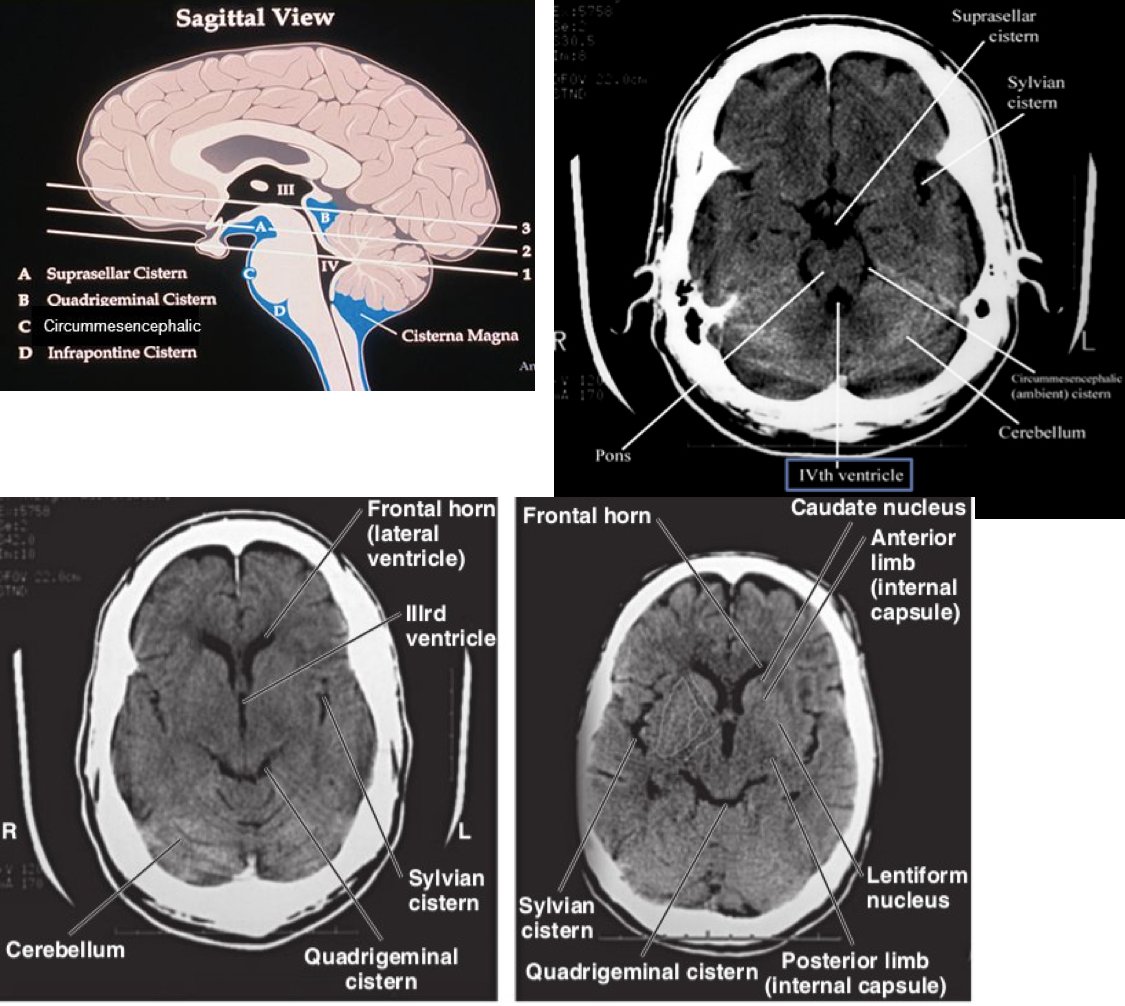

Approach to head CT

A

Blood Can Be Very Bad

Blood

• Extracranial hemorrhage

• Epidural hemorrhage

• Subdural hemorrhage

• Subarachnoid

• Intraparenchymal

• Intraventricular

Cisterns

• Circummesencephalic

• Suprasellar

• Quadrigeminal

• Sylvian

• Look for: effacement, asymmetry, blood

Brain

• Effacement or asymmetry of sulcal pattern

• Grey-white differentiation

• Structural shifts

• Abnormal hypodensity (edema, air)

• Abnormal hyperdesnity (blood, calcification)

Ventricles

• Effacement or asymmetry

• Blood

• Hydrocephalus

Bone

• Fractures

• Soft tissue swelling and air in paranasal sinuses or mastoid air cells should raise suspicion of skull fracture

• Intracranial air = violation of skull and dura